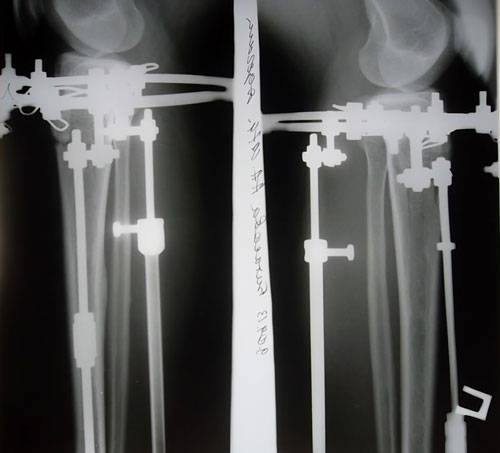

Все мысли о доме, о детках. Никогда не оставляла их так долго без материнской поддержки. Зашла на форум, чтоб еще раз убедиться в красоте своих ножек. Знаю, что наша красавица секретарь Онипко выложит снимки ночью. Все спят, а она занята нашими ножками. Уезжаю отсюда с чувством исполненного долга перед собой- откоректировала пробел природы. Сперва молодость-неимение своих денег, потом детки-нехватка свободного времени, а теперь я занялась собой и привела тело в порядок.

до конца еще не могу поверить-только когда одену брючки-сигаретки- только тогда, видя ровный контур конечностей я вздохну.